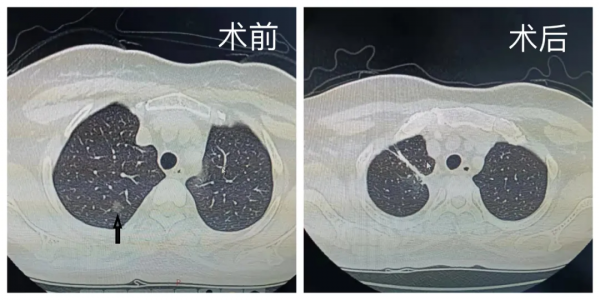

一例中年女性患者,CT的結果顯示:右肺上葉一個磨玻璃結節,位於右肺上葉尖段和後段交界處。這樣的病例要是進行肺葉切除則肺損傷過多,若行常規的肺段切除,那麼無論是切除尖段還是後段,恐怕切緣範圍都難以保證。在微創診療中心主任劉樹庫的帶領下,團隊最終制定了對胸腔鏡單操作孔右肺上葉尖段A亞段合併右肺上葉後段A亞段切除的措施,並順利完成手術。術後在全體醫護人員的精心呵護下,患者快速恢復,順利出院。